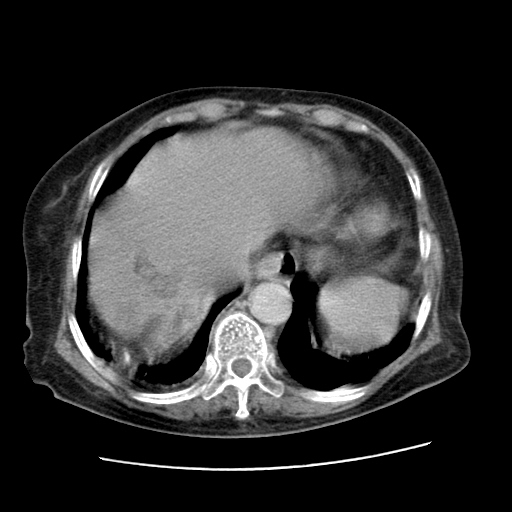

女,77.无不适

肝内胆管扩张,胆囊炎,胆囊窝积液。 右侧胸腔少量积液。

肝右叶肝内胆管结石并肝内胆管扩张

胆总管扩张

右侧胸腔少量积液(也可能是胸膜增厚不过是什么都一样)

肝右叶肝内胆管结石并肝内胆管扩张。另:慢性胆囊炎!胆囊窝积液!

肝右叶肝内胆管结石并肝内胆管扩张。胆总管下段梗阻,考虑壶腹部占位。

肝右叶肝内胆管结石并肝内胆管扩张。胆总管下段梗阻,考虑壶腹部占位。支持